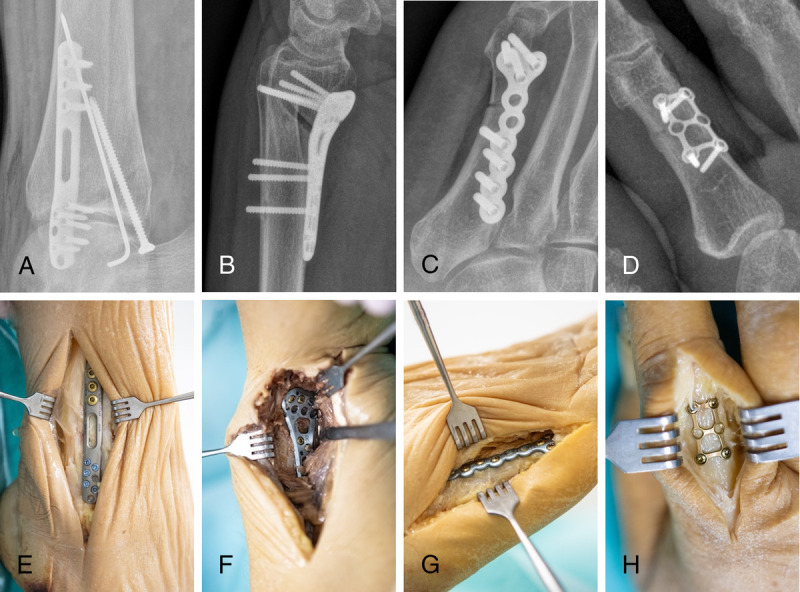

Materials and methods: After surgical fracture induction and subsequent osteosynthesis, 8 cadaveric fracture models (wrist, metacarpus, ankle, metatarsus) were scanned with the prototypical tomosynthesis mode of a multiuse x-ray system. Tomosynthesis protocols at 60, 80, and 116 kV (sweep angle 10°, 13 FPS) were compared with standard radiograms. Five radiologists independently rated diagnostic assessability based on an equidistant 7-point scale focusing on fracture delineation, intra-articular screw placement, and implant positioning. The intraclass correlation coefficient (ICC) was calculated to analyze interrater agreement.

Abstract Image